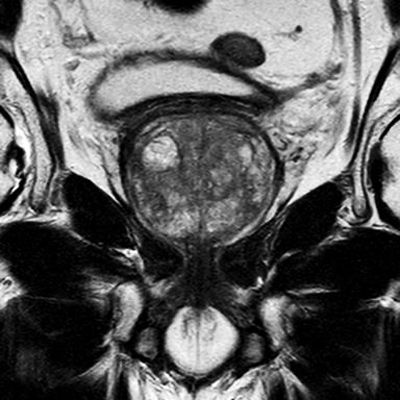

Gli ultimi anni hanno dimostrato ľenorme potenzialità della RMN nella diagnostica del tumore prostatico. Il miglioramento tecnologico delle apparecchiature di Risonanza Magnetica ha consentito di associare alla valutazione morfologica-anatomica della ghiandola prostatica anche studi funzionali (RM-multiparametrica) che consentono di dare informazioni sulla cellularità e sulla vascolarizzazione di eventuali lesioni sospette migliorando notevolmente la specificità della metodica nella diagnosi del tumore prostatico ed aprendo inoltre la possibilità a nuove indicazioni.

Lo studio multiparametrico prevede ľesecuzione di sequenze morfologiche che consentono la corretta visualizzazione delľanatomia prostatica e ľidentificazione di focolai di alterato segnale sospetti; al dato morfologico si aggiunge anche quello funzionale attraverso ľutilizzo di sequenze pesate in diffusione (DWI) e sequenze effettuate dopo somministrazione di mezzo di contrasto (DCE) che consentono di dare informazioni sulla cellularità e sulla vascolarizzazione delľarea sospetta migliorando notevolmente la specificità della metodica nella diagnosi del tumore prostatico ed aprendo inoltre la possibilità a nuove indicazioni.

- nel caso di sospetto clinico-laboratoristico di tumore di prostata (PSA elevato) e biopsie random negative. La RM multiparametrica consente di identificare focolai sospetti su cui effettuare prelievi bioptici mirati. Ľattuale orientamento è quello di utilizzare la RM nella biopsia della prostata in modo attivo, sovrapponendo, con appositi programmi, le immagini di Risonanza a quelle Ecografiche durante ľesecuzione del prelievo bioptico (fusion biopsy);

- nel caso in cui, di fronte alla diagnosi bioptica di tumore a basso rischio (Gleason basso), si decida di optare per la sorveglianza attiva risparmiando ogni tipo di trattamento al paziente; la RM multiparametrica valutando la cellularità e la vascolarizzazione della lesione consente di monitorare i parametri clinici del tumore ed essere pronti a intervenire qualora questi diventassero sfavorevoli.